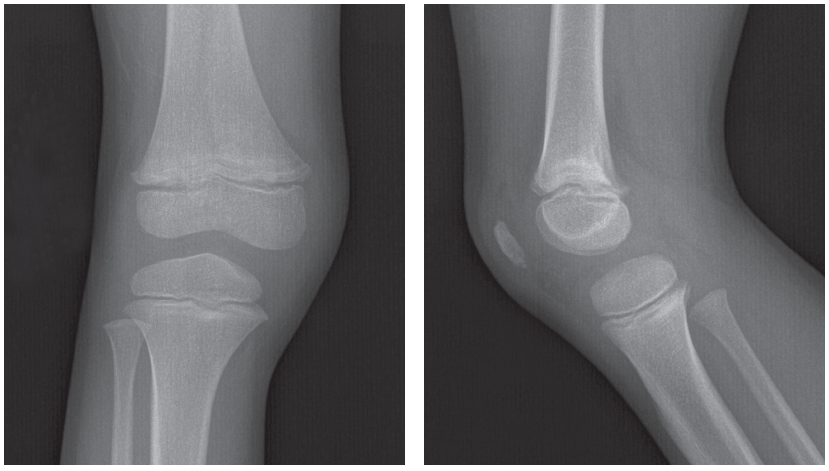

Anteroposterior and lateral views of the right knee are shown.

How do you read these images?

The radiographs show transverse radiolucent metaphyseal bands, uniform and regular across the metaphyses of the distal right femur and proximal right tibia. These transverse bands of radiolucency are suggestive of an infiltrative process such as leukemia. No fracture or dislocation is apparent.